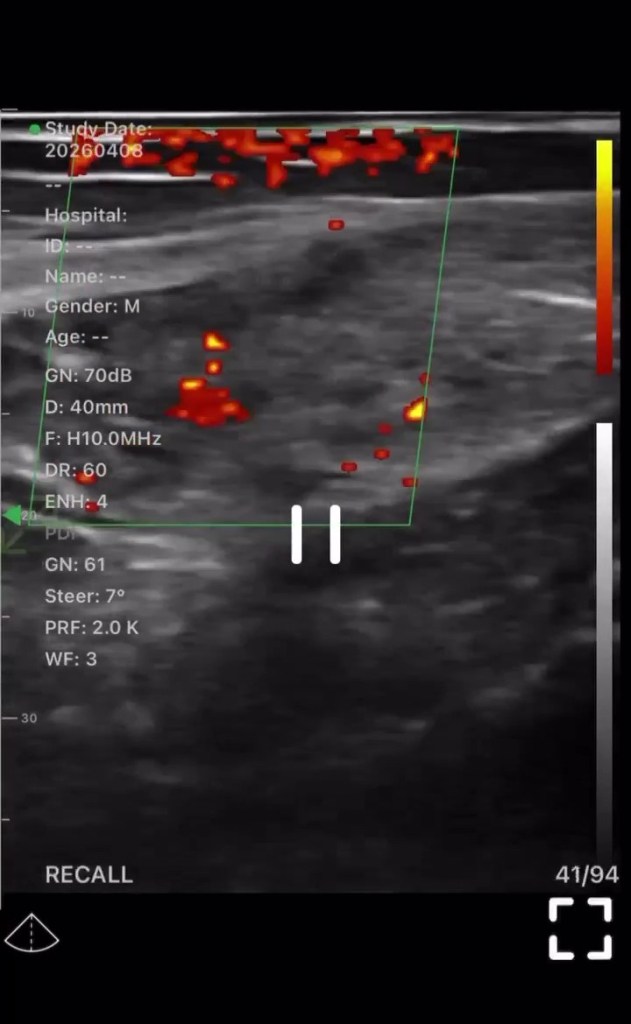

4.難治性が高い場合はエコーによる問診

難治性の高い患者様に対しては、必要に応じて患部をエコーで撮影し、炎症の広がりや深さ、周囲組織への影響などを視覚的に確認します。